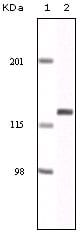

分类: 科研抗体货号: 20072别名: DNM; DNM1应用: WB,IHC反应种属: Human

分类: 科研抗体货号: 20071别名: ECK; EPHA2应用: WB,IHC反应种属: Human